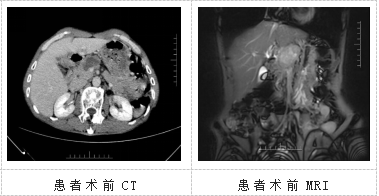

患者姚某某,来自曲靖陆良,两个月前突然感觉上中腹部疼痛,且近期体重下降明显,已下降7kg,在家人的陪同下辗转于多家医院查找原因。经过一系列检查,考虑为胰腺癌,在朋友的推荐下,患者来到昆明医科大学第二附属医院肝胆胰外科三病区就医。

肝胆胰外科三病区许宁医生接诊后,认真研究患者病历;科室负责人龙奎主持全科室进行术前讨论,同时进行院内MDT会诊后,制定了手术治疗方案。经过周密的术前准备后,2023年7月12日,昆医大附二院肝胆胰外科三病区手术团队联合心血管外科团队、麻醉团队、手术室护士团队,为患者实施了手术。手术中探查发现,肿瘤位于胰颈体部,大小约5X4X3cm大小,肿瘤侵犯包绕肝总动脉近段及门静脉起始部致肝总动脉搏动微弱、门静脉变细、肠系膜上静脉增粗,若要达到根治标准则必须在全胰十二指肠切除术的基础上连同腹腔干及门静脉一并切除,并且彻底清扫后腹膜淋巴结。手术极其复杂,难度大、风险高,对术者技术水平要求极高。术中,手术团队沉着冷静,对血管进行精细解剖及切除并行门静脉主干的人工血管置换术及肝总动脉与腹主动脉的精细吻合。此次手术术中出血300ml,历时6小时。肝胆胰外科精湛的医技避免了术后的出血、血管吻合口狭窄、血栓形成等严重并发症的发生。患者术后恢复平稳,术后10天开始拔除腹腔引流管,术后15天顺利出院。